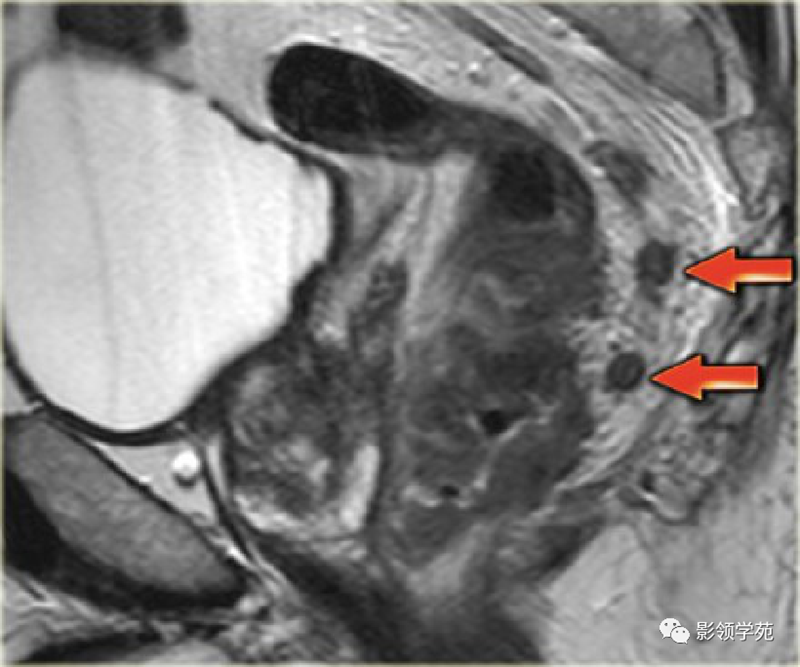

1、影像学检查:如X线胃肠道钡餐造影、CT检查、MRI检查、经直肠超声检查。腹部X线检查适用于伴发急性肠梗阻病人,可见梗阻部位上方的结肠有充气胀大现象。直肠癌术前行直肠MRI为常规检查项目,是术前分期的重要依据。

直肠癌淋巴结转移磁共振影像